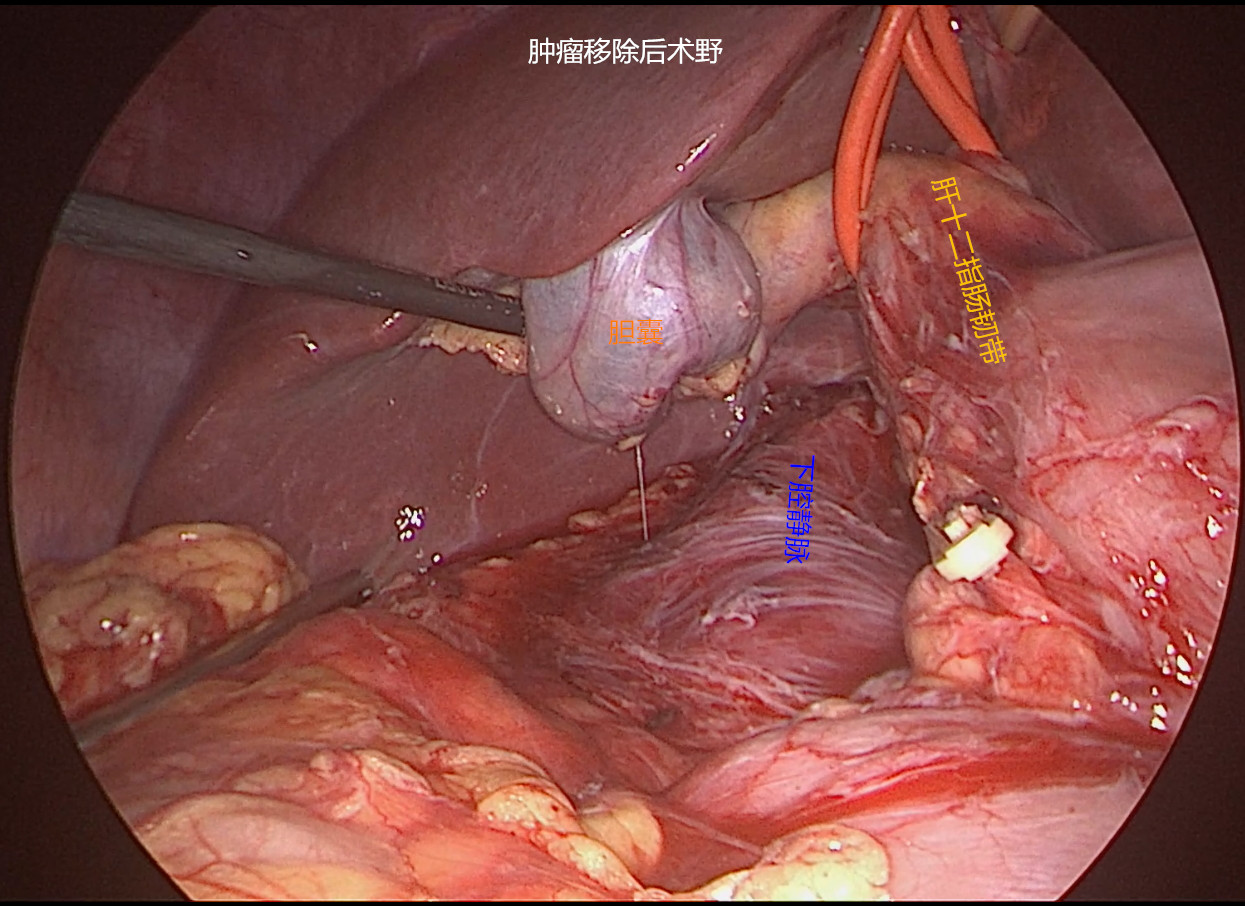

患者女性,45岁,体检发现后腹膜占位2月。CT提示:“胰腺后方可见约63*90mm混杂密度肿块影,内可见囊实性区及脂肪、牙齿,增强扫描实性区动脉期轻度强化,门脉期明显强化,边界清;腹腔干、肠系膜上动脉受压移位,考虑畸胎瘤诊断”。患者后腹膜占位诊断明确,肿瘤较大周围脏器受压,手术指征明确,拟行腹腔镜手术探查。手术困难所在:1.病变位于肝十二指肠韧带、十二指肠、胰头及横结肠后方暴露困难;2.毗邻关系复杂,病变周围与肝脏、胆囊、胆总管、横结肠、胃窦、十二指肠及胰头等重要器官毗邻;3.周围大血管多,病变与门静脉、肝总动脉、腹腔干、肠系膜动静脉、下腔静脉及左肾静脉关系密切,易导致术中大出血;4.病变系囊实性肿块牵引提拉困难。今经过团队两个小时的努力顺利切除肿瘤,术中出血约100ml。感谢麻醉师、护士及团队的辛勤付出,祝患者早日康复。